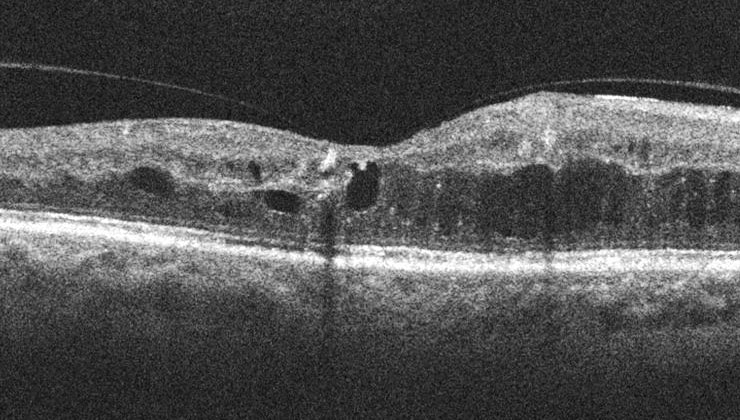

El edema macular consiste en el acúmulo de líquido en la mácula, la parte más importante de la retina, responsable de la visión central y de detalle.

El edema macular se debe al escape de fluido de los vasos sanguíneos retinianos, ya sea porque están dañados o son anómalos y sus paredes se vuelven más permeables o demasiado delgadas.

Como consecuencia de la fuga o extravasación de líquido, la mácula se “encharca”, se engruesa y se inflama. El resultado es una degeneración progresiva de las células fotorreceptoras que nos permiten ver, cuya mayor concentración se encuentra en esta zona central de la retina.